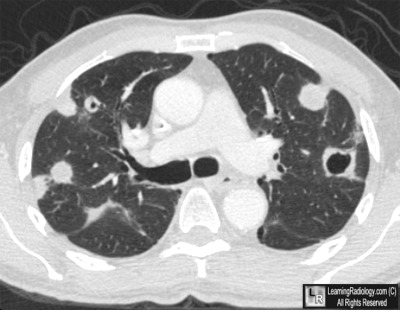

Additional Images-Axial CT scan image of chest

Axial CT scan image of chest

Cavitary Metastases from Esophageal Carcinoma

• Metastases to the lung occur in about 30% of all malignant disease

• Routes of spread include hematogenous, lymphangitic and direct extension

• Most metastatic lung nodules develop through hematogenous spread

• Primary lung carcinomas cavitate more frequently than metastatic lesions to the lung

• Most cavitary metastases are epithelial in origin